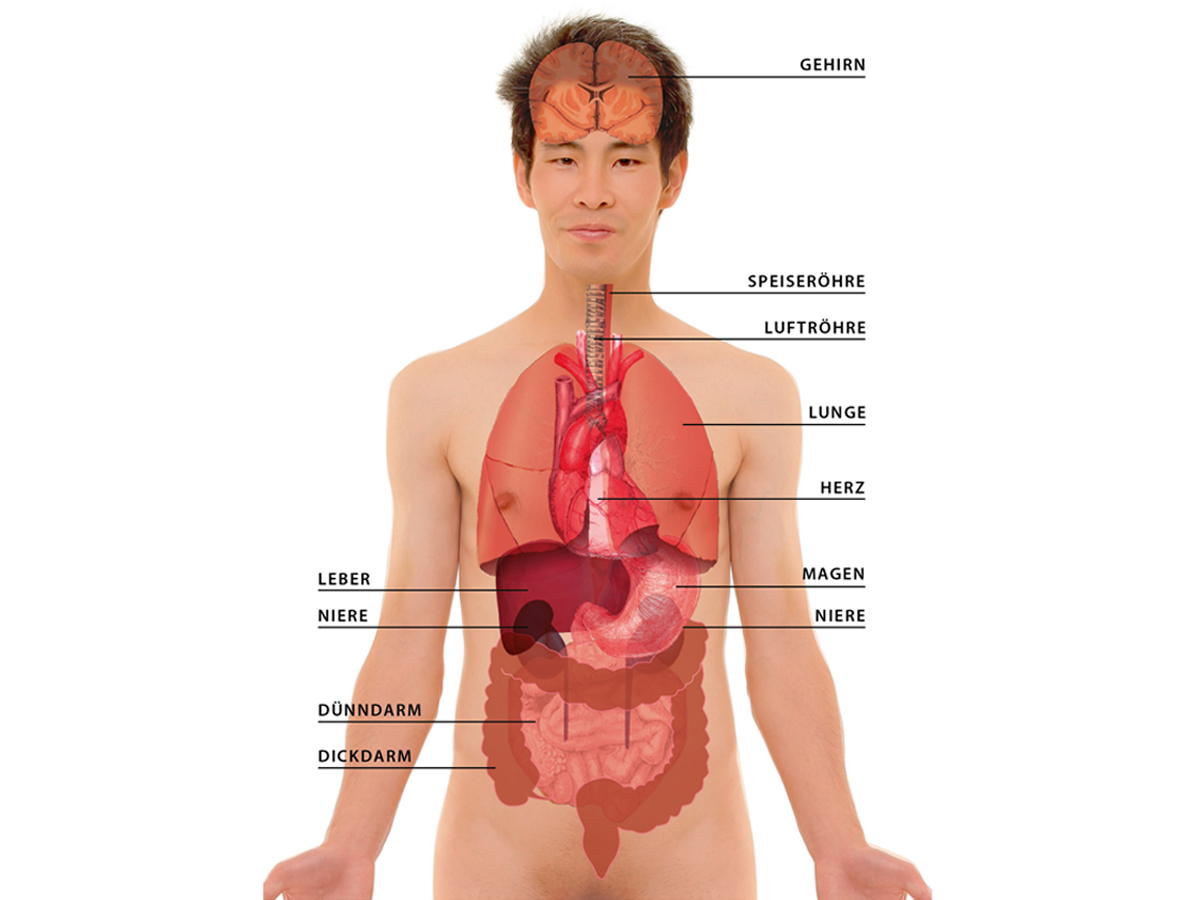

-n.+das+Ohr" width="550" alt="Tief in ihren Körper" title="Tief in ihren Körper">-en.+der+Mund.+die+Nase.+der+Hals..jpg" width="550" alt="Tief in ihren Körper" title="Tief in ihren Körper">